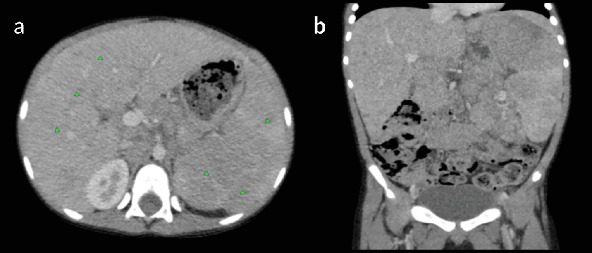

t细胞/组织细胞丰富的大b细胞淋巴瘤(THRLBCL)是弥漫性大b细胞淋巴瘤(DLBCL)的一种罕见的侵袭性亚型,在儿童中并不常见。在这里,我们提出一个8岁的男性病例,他有3个月的低度间歇性发热史,体重明显减轻,食欲不振,腹部肿胀。检查显示脾肿大,腹部中部可触及肿块,实验室结果显示双氧体减少。影像学显示肝脾肿大,弥漫性低密度肝脏和脾脏病变,肠系膜和腹膜后淋巴结病变。肠系膜肿块的核心穿刺活检证实了诊断,组织病理学显示分散的大单核和双核细胞,背景是小淋巴细胞和组织细胞。免疫组织化学显示CD45、CD20和EMA呈阳性,CD30、CD15和Bcl-2呈阴性,排除了其他诊断,如结节性淋巴细胞显性霍奇金淋巴瘤(NLPHL)和经典霍奇金淋巴瘤(cHL)。患者最初通过环磷酰胺、长春新碱和泼尼松(COP)的前期方案稳定,随后用R-COPADM(利妥昔单抗、环磷酰胺、长春新碱、泼尼松和甲氨蝶呤)诱导和巩固。治疗后影像学显示淋巴结病变和肝脾肿大明显消退,无残留或复发疾病。在随访中,患者仍处于临床缓解期,无进展迹象。该病例强调了早期识别,详细的组织病理学评估以及免疫组织化学在准确诊断儿童THRLBCL中的作用,确保及时开始有效治疗并改善这种罕见的儿科恶性肿瘤的预后。

T-cell/histiocyte-rich large B-cell lymphoma (THRLBCL) is a rare and aggressive subtype of diffuse large B-cell lymphoma (DLBCL) that is uncommon in children. Here, we present the case of an 8-year-old male with a 3-month history of low-grade intermittent fever, significant weight loss, loss of appetite, and progressive abdominal swelling. Examination revealed splenomegaly and a palpable midabdominal mass, with laboratory findings showing bicytopenia. Imaging demonstrated hepatosplenomegaly, diffuse hypodense liver and spleen lesions, and mesenteric and retroperitoneal lymphadenopathy. A core-needle biopsy of the mesenteric mass confirmed the diagnosis, with histopathology revealing scattered large mononuclear and binucleate cells in a background of small lymphocytes and histiocytes. Immunohistochemistry showed positivity for CD45, CD20, and EMA and negativity for CD30, CD15, and Bcl-2, excluding alternative diagnoses such as nodular lymphocyte-predominant Hodgkin lymphoma (NLPHL) and classical Hodgkin lymphoma (cHL). The patient was initially stabilized with a prephase regimen of cyclophosphamide, vincristine, and prednisone (COP), followed by induction and consolidation with R-COPADM (rituximab, cyclophosphamide, vincristine, prednisone, and methotrexate). Posttreatment imaging revealed significant resolution of lymphadenopathy and hepatosplenomegaly, with no residual or recurrent disease. At follow-up, the patient remains in clinical remission with no signs of progression. This case highlights the importance of early recognition, detailed histopathological evaluation, and the role of immunohistochemistry in accurately diagnosing THRLBCL in children, ensuring timely initiation of effective therapy and improving outcomes in this rare pediatric malignancy.